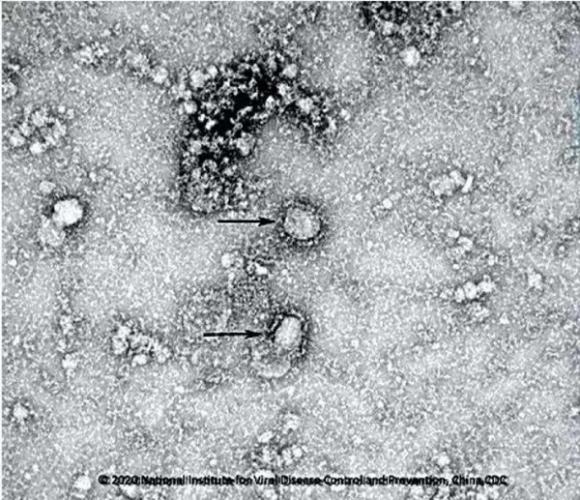

Cận cảnh virus corona.